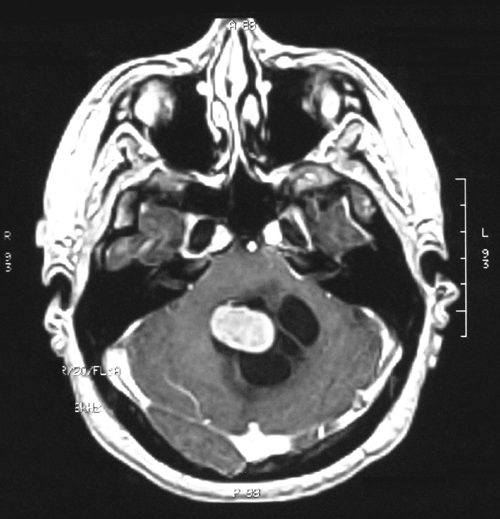

On T1-weighted MR image (Panel A) with gadolinium enhancement, there is a midline cystic lesion with a well-demarcated, oval, mural nodule that has smooth margin. The nodule seems to have a thin and brightly enhancing rim. The core of the nodule shows heterogeneous enhancement. On T2-weighted MR image (Panel B), the nodule is hyperintense to the grey matter and is heterogeneous. No significant edema is demonstrated in the parenchyma surrounding the tumor.

The brain invasion without association with edema that can be demonstrated on T2-weighted MR image is a small surprise.   Although the morphologic features are suggestive of choroid plexus papilloma, the possibility of a metastatic low-grade carcinoma has been entertained during intraoperative consultation.